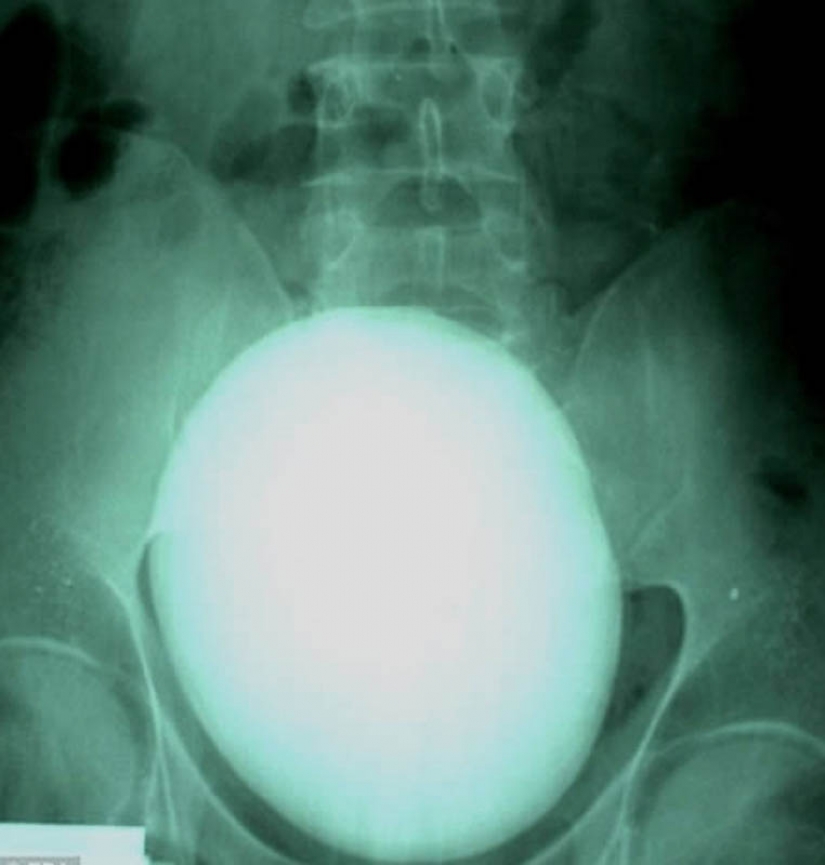

17. Aquí es una de 15 cm de piedra en el riñón de pesaje 1.1 kg fue eliminado de la paciente de Hungría.